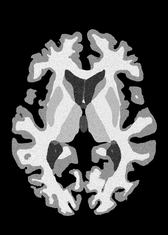

4.2 Registration to a 100 micron ex-vivo brain MRI volume

To showcase the efficacy of our method on real large scale images, we register a 250 in-vivo MRI image (Lüsebrink et al., 2017) to a 100 ex-vivo FLASH human brain volume (Edlow et al., 2019). This represents an inverse problem with more than 11.2B optimizable parameters (compared to 20M for clinical datasets), or 44.8GB of GPU memory. The entire problem does not fit on most GPUs, necessitating distributed multimodal registration. We optimize a composite transform - affine followed by a diffeomorphic mapping; details can be found in Section E.1. Multimodal deformable registration took 58 seconds on 8 NVIDIA A6000 GPUs, which is unprecedented at this resolution. Fig. 6 shows qualitative results, highlighting the ability to register highly detailed structures such as cerebellar white matter; these structures are not visible at macroscopic scales. The resultant advantages of performing registration at this scale can allow researchers to characterize the neuroanatomy at microscopic resolutions and allow morphometric analysis of cortical layers and subcortical nuclei among other structures.